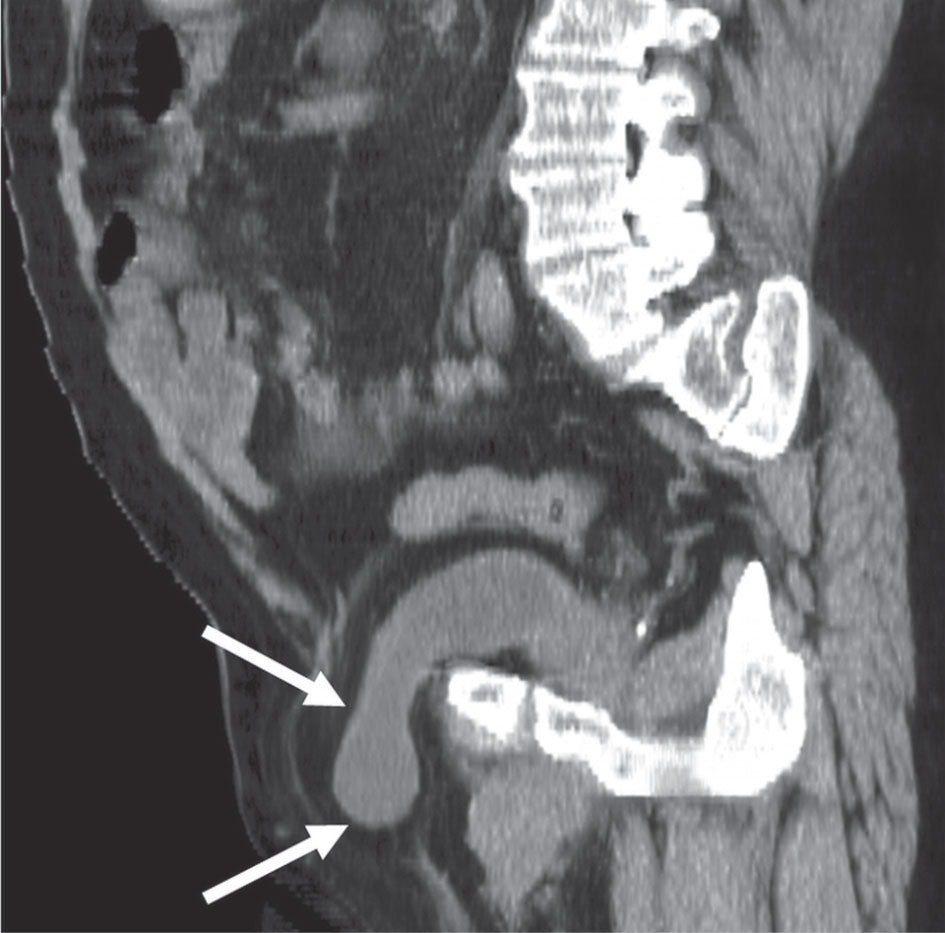

من أعراض النواسير المثانية المعوية (إضافة إلى الأعراض المعوية للداء المسبب) التبول المتكرر مع التهاب بولي لا يمكن السيطرة عليه دوائياً. وكثيراً ما يظهر في البول قليل من محتويات الأمعاء الدقيقة أو الغليظة أو مرور هواء مع التيار البولي. يؤكد التشخيص بالتنظير المعوي أو تصوير الأمعاء الظليل أو تصوير المثانة الظليل (الشكل 7)، بيد أن التنظير المثاني قد يكون الأكثر تأكيداً.

أما في النواسير النسائية؛ فغالباً ما يكون السلس مصحوباً بالتهاب مثاني وتخرش في الجلد المحيط بالفتحة التناسلية نتيجة تعرضه للتماس المستمر مع البول. يؤكد التشخيص بفحص المهبل المباشر أو بتصوير الجهاز البولي الظليل (الشكل 8)؛ مما يمكّن من رؤية النواسير الحالبية المثانية. كما يمكن وضع صباغ الميثيلين الأزرق في المثانة ومشاهدته وهو يخرج إلى المهبل في أثناء الفحص المهبلي. وهنا أيضاً يحدد التنظير المثاني وجود الناسور وموقعه ضمن المثانة. هناك نواسير نادرة نسبياً تحدث بين المثانة والرحم بعد العمليات القيصرية يكون تشخيصها بالتنظير أو التصوير المثاني غالباً.